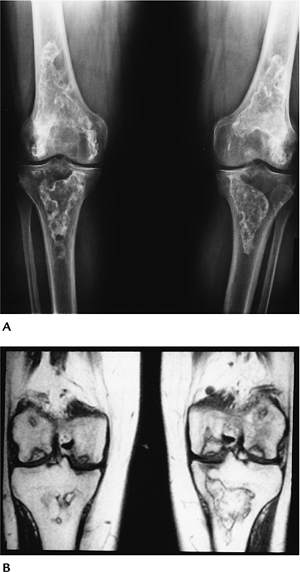

FIGURE 12-8 Eosinophilic granuloma. (A) AP radiograph of the femur showing a lytic lesion with endosteal scalloping and periosteal reaction. AP (B) and lateral (C) radiographs of the spine with marked compression (vertebra plana) of T6.